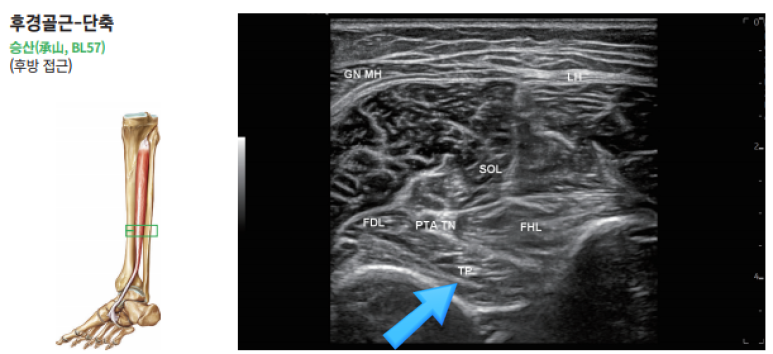

@ 초음파로 보는 알짜근육학

한의학에 "조해혈(照海穴)"이라는아주 중요한 혈자리가 있습니다.

안쪽 복숭아뼈 바로 아래 움푹 들어간 곳인데요.

이 곳은 족소음신경 경락이 지나가는 길목이며,

놀랍게도 해부학적으로 이 조해혈 바로 아래로

후경골근건이 지나갑니다.

경혈초음파 "조해혈"

이 "조해혈" 주변에 초음파 프로브를 대고

경혈의 표준 초음파 영상과 비교하며,

문제를 확인합니다.

특히 해당 혈자리 주변은 후경골근건 외에도

복잡한 구조물이 많기 때문에

통증의 원인이 정말 후경골근건이 맞는지

감별하는 것이 매우 중요합니다.